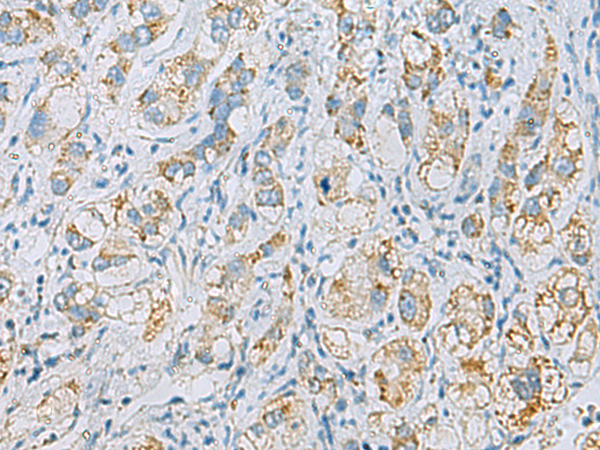

分类: 科研抗体货号: P10355别名: ACS; LLPL; LPLA2; LYPLA3; GXVPLA2应用: IHC反应种属: Human, Mouse, Rat